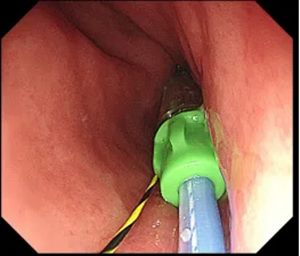

▲ 通过导丝植入支架

这次,在小李体内,这一过程被巧妙地“打断”了。在消化内镜中心,为他实施的胃转流支架系统置入术,为他的肠道设置了一个 “智能分流系统”。

这项创新的内镜下减重技术,通过在十二指肠及空肠上段置入一个特殊的、像袖套一样的支架,让食物物理性地“绕过”这段肠道,使其不再与肠液充分接触。这就像在肠道内搭建了一条“高架路”,让来自胃的食物快速通过,减少了与消化液的“交汇”。